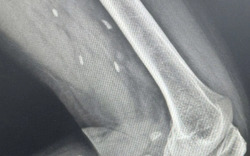

• Đang ăn sữa chua, người phụ nữ nuốt chiếc thìa dài 17cm vào bụng

Đang ăn sữa chua, người phụ nữ nuốt chiếc thìa dài 17cm vào bụng

Sức khỏe -

Một người phụ nữ đã vô tình nuốt phải một chiếc thìa dài 17cm khi con chó của cô nhảy lên đùi trong lúc cô đang ăn sữa chua.